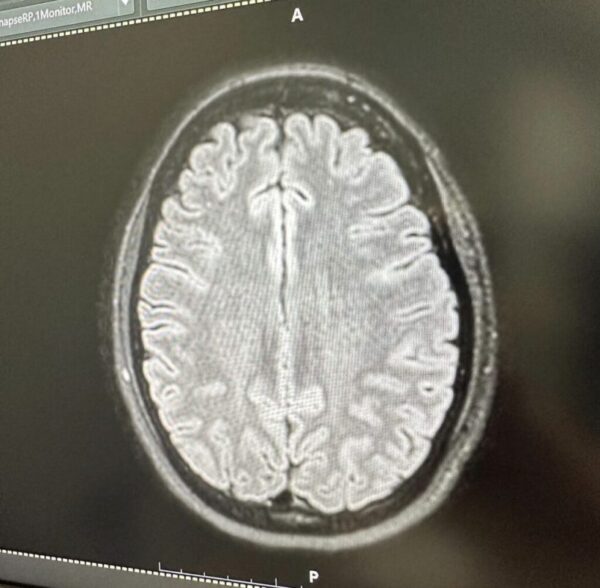

“MRI สมอง เพราะปวดหัวมาก สรุปเป็นไมเกรน นึกว่าเป็นเนื้องอก ลุ้นแทบตาย โล่งอก คุณหมอให้ยาฉีดที่ขาแต่เป็นยาฉีดสำหรับไมเกรน ดีขึ้นเลย แต่ต้องฉีดต่อเนื่อง 3-6 เดือน ดีจังไม่ต้องทนปวดกินยาแล

Cr_ig: bong_kod_tak